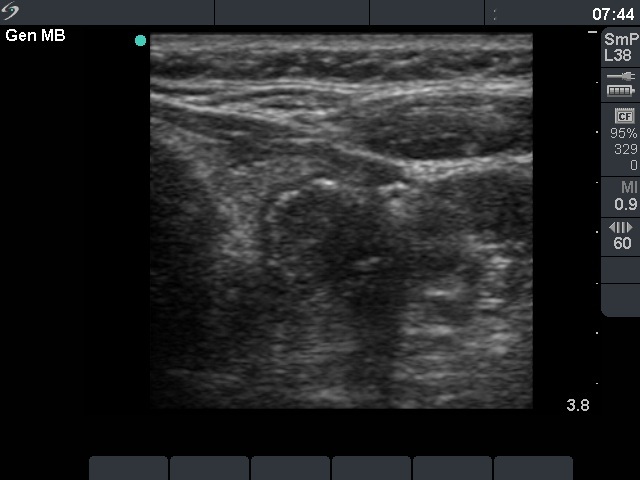

Benign colloid goiter (cytological diagnosis) |

There is a calcification in the dorsal part of the lesion.